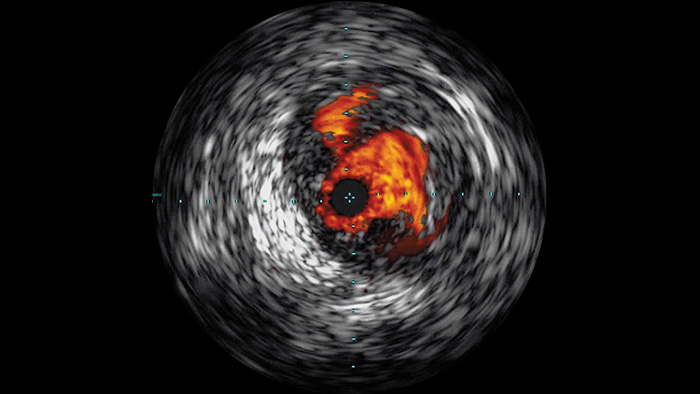

Внутрисосудистое ультразвуковое исследование (ВСУЗИ) — это технология визуализации с использованием катетера, которая позволяет визуализировать кровеносные сосуды изнутри и помогает определить наличие и степень заболевания. С помощью ВСУЗИ можно подобрать и осуществить подходящую медицинскую процедуру индивидуально для каждого пациента, а также убедиться в успешности лечения.

Создает изображения высокого разрешения, позволяя детально рассмотреть сосуды и таким образом обеспечивая проведение точного курса лечения, навигации и последующего наблюдения за пациентом.